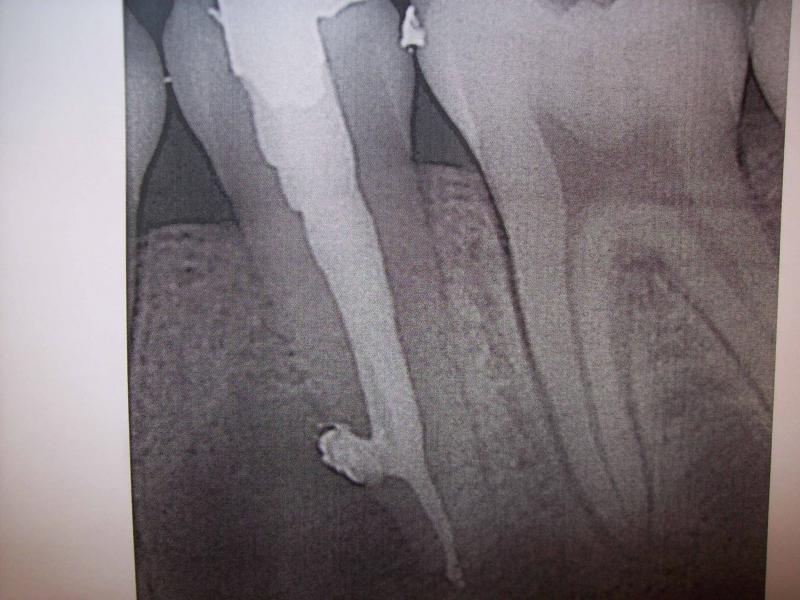

DR JET LOVES ROOT CANALS

General Dentist,  Performs Root Canals ONLY - Microscope Trained Dentist

"DR. JET'S MISSION IS TO PERFORM  ROOT CANALS FOR A REDUCED FEE USING THE LATEST TECHNOLOGY  AND TECHNIQUES TO SERVICE THE MANY PEOPLE WHO ARE UNINSURED OR UNDER-INSURED GIVING EVERYONE AN OPPORTUNITY TO SAVE THEIR TOOTH!"

**PLEASE BE AWARE THAT  A ROOT CANAL IS AN ATTEMPT TO SAVE YOUR ALREADY DAMAGED TOOTH.  THERE IS NO GUARANTEE THAT ANY TOOTH CAN BE SAVED BUT DR JET WILL DO HIS BEST TO HELP YOU. THE OTHER OPTION IS TO EXTRACT YOUR TOOTH